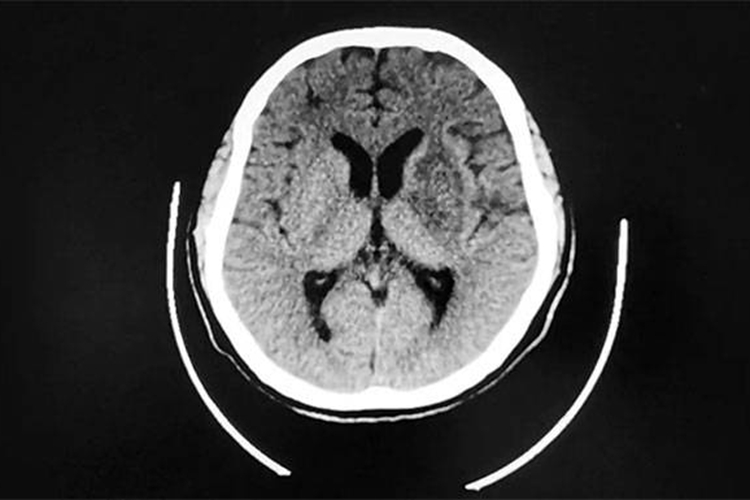

多数患者发病24小时后脑CT逐渐显示低密度梗死灶,发病后2-15日可见均匀片状或楔形的明显低密度灶。MRI可清晰显示早期缺血性梗死,梗死灶T1呈低信号、T2呈高信号。